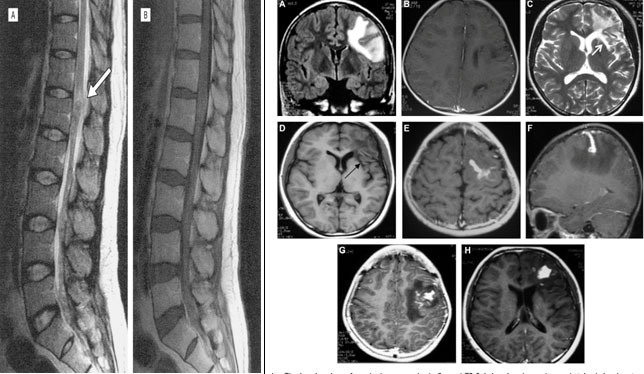

20.Moon W.K., Chang K.H., Cho S.Y., Han M.H., Cha S.H., Chi J.G., et al. Cerebral sparganosis: MR imaging versus CT features. Radiology. 1993;188(3):751-757.

21.Song T., Wang W.-S., Zhou B.-R., Mai W.-W., Li Z.-Z., Guo H.-C., et al. CT and MR characteristics of cerebral sparganosis. AJNR Am. J. Neuroradiol. 2007;28(9):1700-1705.

33.Chang K.H., Cho S.Y., Chi J.G., Kim W.S., Han M.C., Kim C.W., et al. Cerebral sparganosis: CT characteristics. Radiology. 1987;165(2):505-510.

34.Chang K.H., Chi J.G., Cho S.Y., Han M.H., Han D.H., Han M.C. Cerebral sparganosis: analysis of 34 cases with emphasis on CT features. Neuroradiology. 1992;34(1):1

35.Liao H., Li D., Zhou B., Liu J., Li Y., Liu H., et al. Imaging characteristics of cerebral sparganosis with live worms. J. Neuroradiol. J. Neuroradiol. 2016;43(6):378-383.

36.Meng Y., Kuang Z., Liao L., Ma Y., Wang X. Case report: morphologic and genetic identification of cerebral sparganosis. Am. J. Trop. Med. Hyg. 2019;101(5):1174-1176.

37.Zhang P., Zou Y., Yu F.-X., Wang Z., Lv H., Liu X.-H., et al. Follow-up study of high-dose praziquantel therapy for cerebral sparganosis. PLoS Negl. Trop. Dis. 2019;13(1)

38.Li H.-X., Luan S.-H., Guo W., Hua L.-Y., Zhu H.-D., Deng J.-J., et al. Sparganosis of the brain: a case report and brief review. Neuroimmunol. Neuroinflammation. 2017;4(1):238–242.